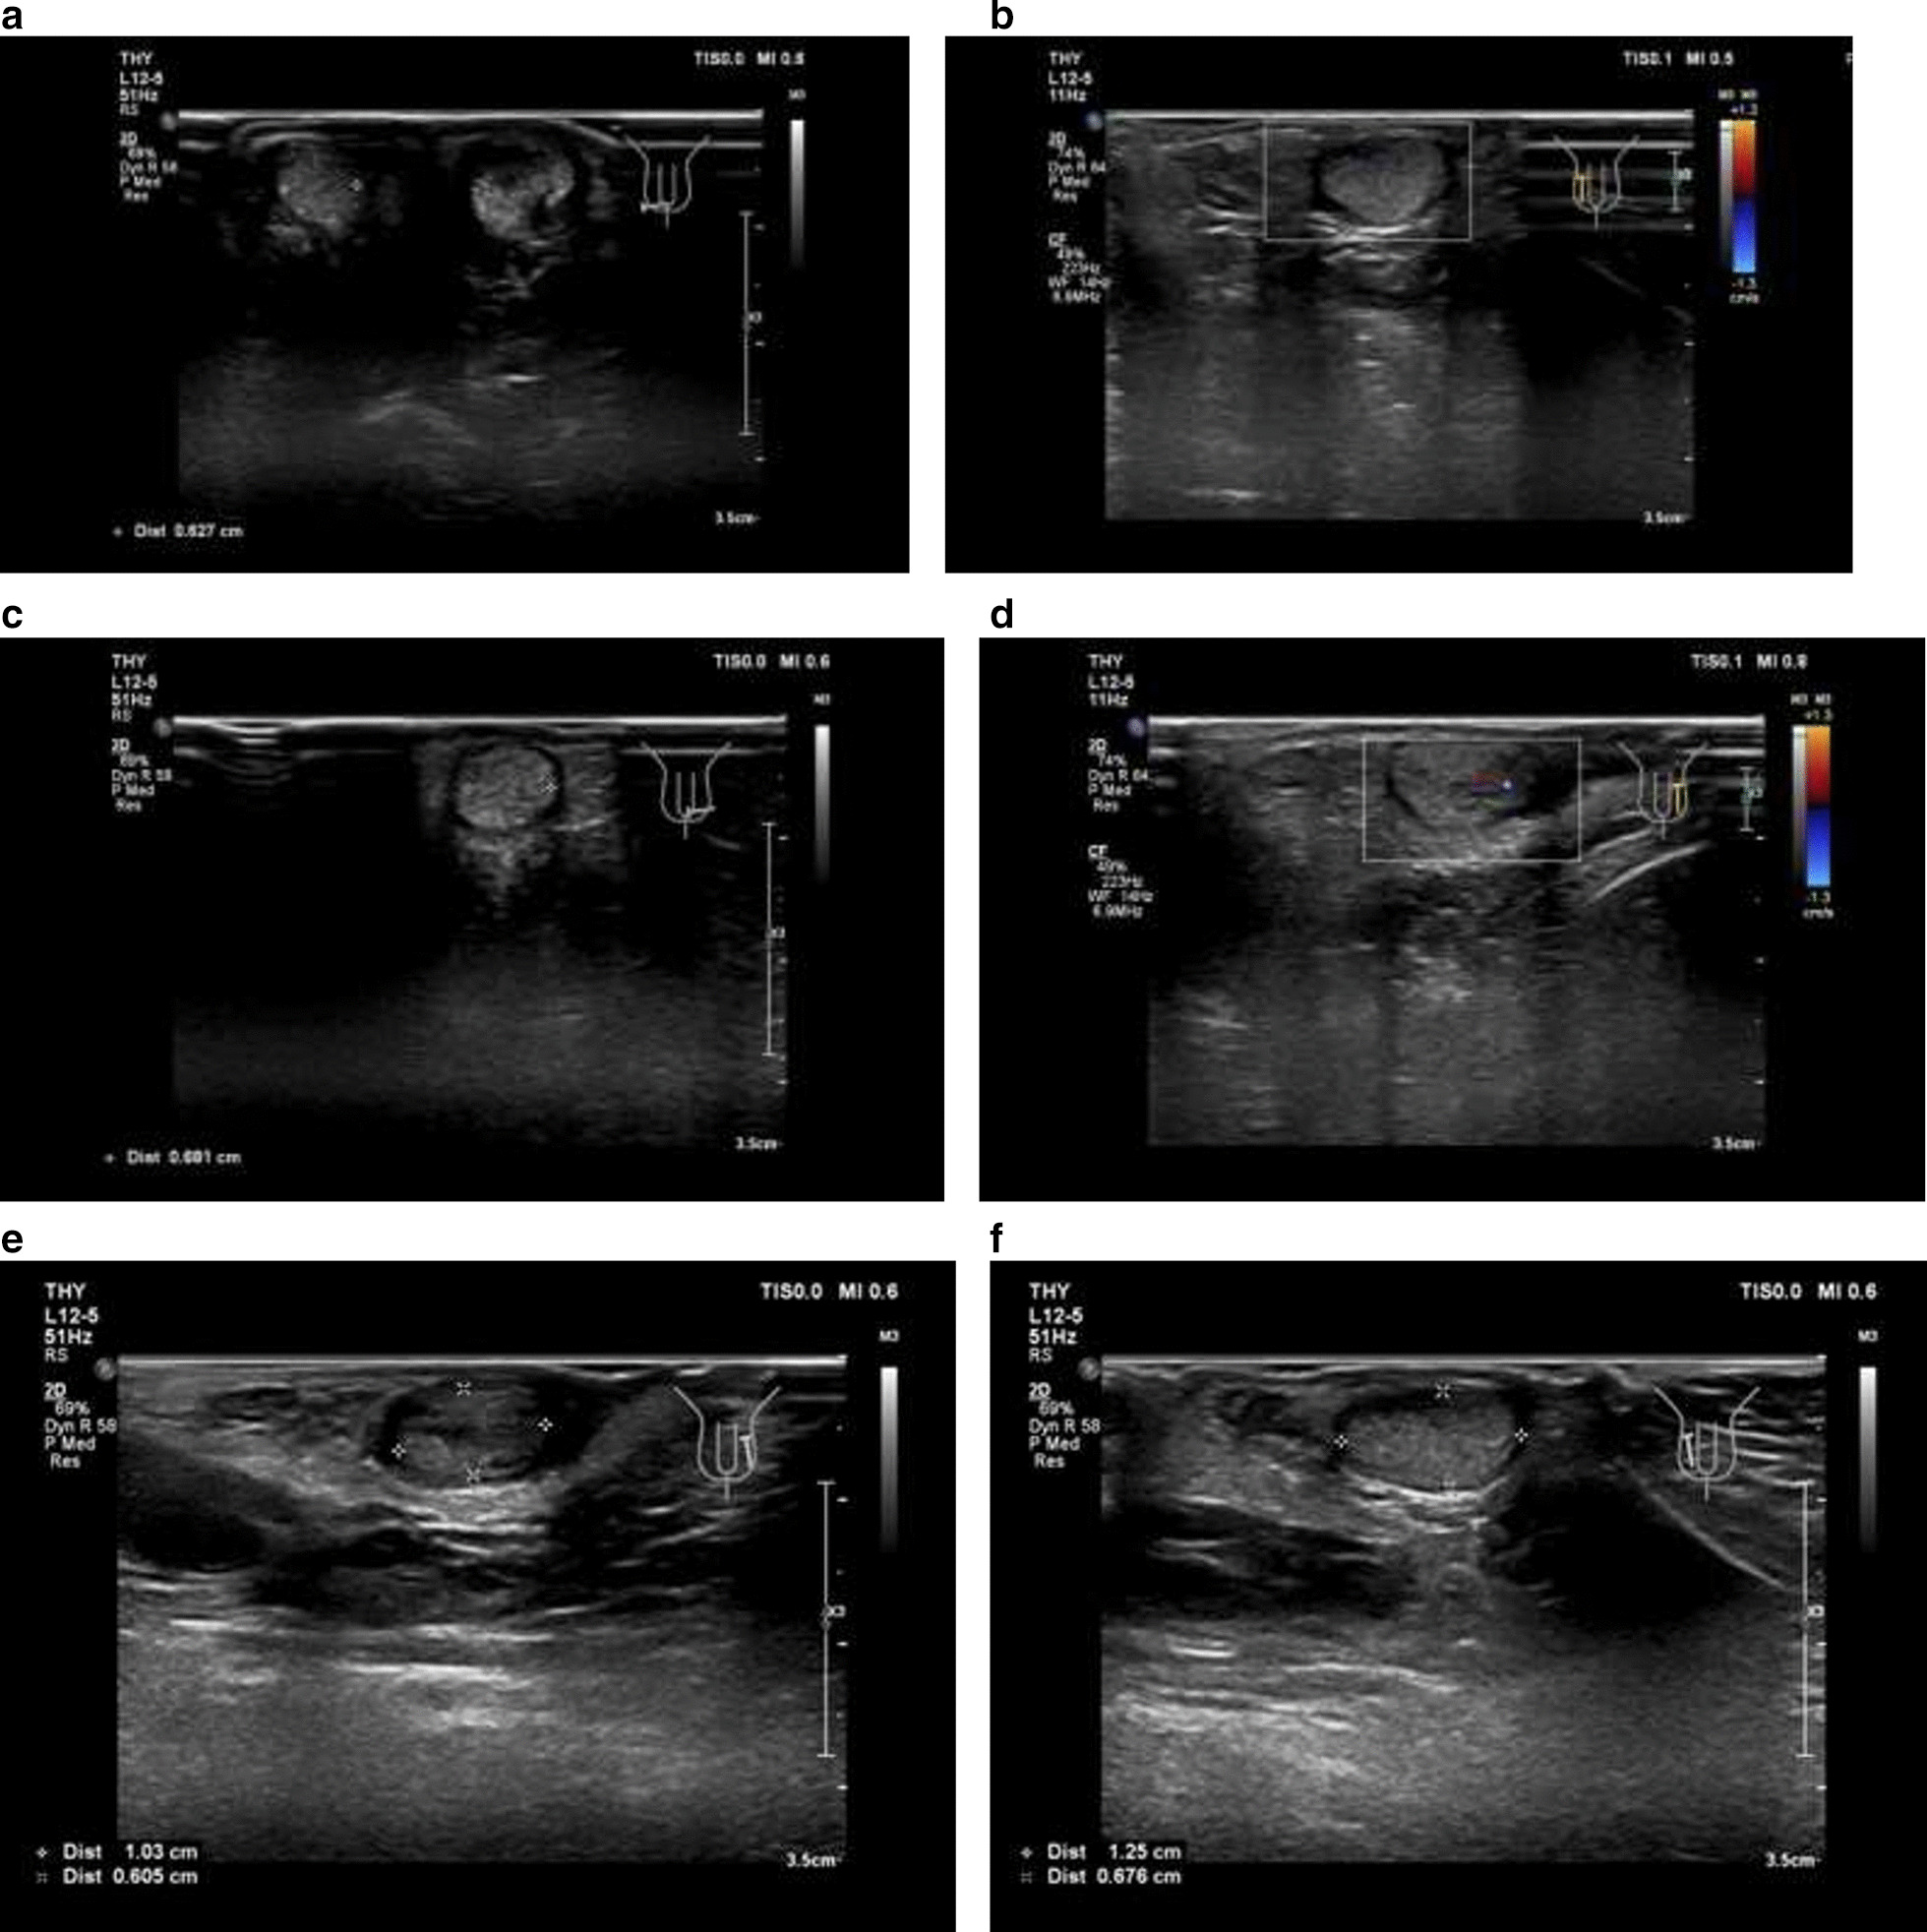

Stage 2 of laparoscopic staged Fowler-Stephen orchiopexy for the left testis was performed 7 months later (March 12, 2019), the left testis descended into the scrotum. The residual spleen tissue was cut from the left testis (Fig. 2e) and post-operative biopsy confirmed that it was accessory spleen tissue. Ultrasound monitoring immediately after surgery revealed that both testis had normal shapes and good blood supply, it also visualized smooth tunica vaginalis and multiple hyperechoic spots without acoustic shadows indicating possible testicular microlithiasis (Fig. 3a–d). B-mode ultrasound taken 1 month later (April 20, 2019) revealed that both testes were in the scrotum and that the left and right testes had a size of 1.3 × 0.7 × 0.6 cm and 1.3 × 0.8 × 0.7 cm, respectively. Both testes had healthy blood supply and the spleen had a normal shape. The patient had an uneventful recovery and suffered no adverse or unanticipated events. Follow-up ultrasound 1 year after the surgery revealed no obvious abnormalities in the shapes of the testes or their blood supply (Fig. 3e, f) and the patient’s penis and scrotum had normal appearance (Fig. 1c).

Fig. 3.

Post-operative ultrasound of the testes. a The right testis; b post-operative Doppler image of blood supply for the right testis; c left testis; d post-operative Doppler image of blood supply for the left testis; e and f follow-up ultrasound 1 year after the surgery showed that the left and right testes had a size of 1.0 × 0.6 × 0.6 cm and 1.3 × 0.7 × 0.7 cm, respectively, both with a homogeneous echogenic appearance and normal blood supply